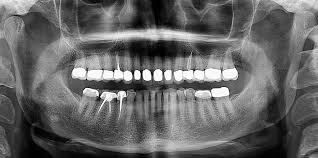

DENTAL THERAPY

A BRIEF INFORMATION ON THE DENTALTHERAPY DEPARTMENT AT NIGERIAN NAVY COLLEGE OF HEALTH SCIENCES OFFA

The Nigerian Navy School of Health Sciences Offa was established to train middle level manpower for Naval Medical Services. Presently, the school runs 7 medical professional courses in Pharmacy, Medical Laboratory Science and Environmental Health. Others include Health Information Management, Physiotherapy and Radiography at Technician and Diploma level. Recently, the Commandant of the School in person of Captain ID Nuruddeen conceived and established the Dental Therapy Department with the aim of training Dental Therapists at National Diploma (ND) and Higher National Diploma (HND) level. Therefore the Dental Therapists Registration Board of Nigeria (DTRBN) was invited to assess the department for accreditation.

The Dental Therapy curriculum includes instructive, laboratory and clinical practice sufficient to graduate competent clinicians who are capable of practicing contemporary dental therapy procedures. The Programme is design to give the students an opportunity to learn and be grounded in the Dental Therapy training, thereby making them relevant in the NN and Tri-Service Hospitals and the country in general.Furthermore, the visit of the Dental Therapists Registration Board of Nigeria (DTRBN) team from 27-28 Jul 16 was quite successful. During this period several observations were made and the school with the support of the NHQ effected changes accordingly. Consequently, the report of the assessment team was forwarded to the school on the 4 Aug 16 indicating an official approval by the Board to admit and commence the training of Dental Therapist at ND leading to HND level with effect from 2016/2017 academic session. Accordingly, the pioneer students of the department were admitted in October 2016. Also, the DTRBN visit was followed by the National Board for Technical Education (NBTE) after an advisory visit in December 2017. Efforts are currently in place to invite the DTRBN and NBTE for full accreditation and award of HND for the Dental programme in the school.

The Dental Therapy department in the school now offers a unique programme, which provides quality educational experiences for undergraduate Dental Therapy Students. ThisProgramme is design to give the students an opportunity to learn and develop in a friendly, caring and professional environment.This would enable the students upon graduation to launch themselves into the responsibilities of a working life with confidence and competence.On completion, the students would be awarded an HND degree in Dental Therapy. This would be followed by a professional examination to be conducted by the DTRBN which will lead to registration and license to practice as a professional dental therapist.

The duration of the DentalTherapy Course isa straight 4 years. This will be followed immediately with a one year internship and a mandatory one year NYSC for civilians while military personnel will be exempted from the NYSCprogramme. The programme is designed to encompass new topics obtainable in the modern training of dental therapistas enshrined in the approved curriculum by the DTRBN and NBTE.During the 4 years, the students are scheduled to proceed for practical attachment inDental Clinic/Hospital.